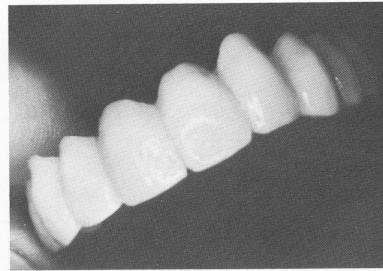

Fig. 11-184. The acrylic full arch splint.

3 Maxillary acrylic full arch splint